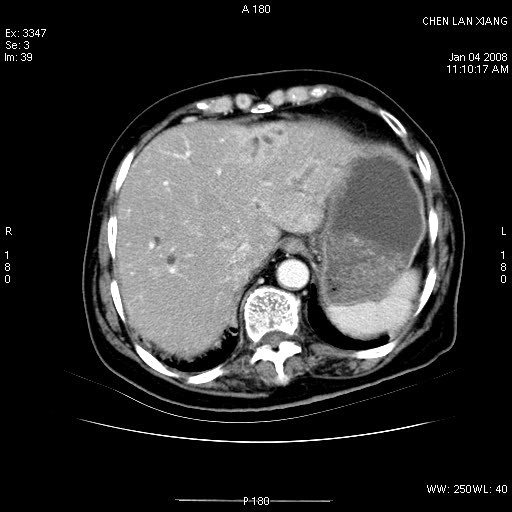

标题: CT11180:女,76岁,腹痛3-4天 [打印本页]

标题: CT11180:女,76岁,腹痛3-4天

女,76岁,腹痛3-4天,b超示:肝内实性肿物,胆囊强回声,胆总管扩张.

考虑:1、胆总管下端结石伴梗阻性肝内外胆管扩张(肝左叶外侧段肝内胆管多发结石、胆管炎);

2、肿囊癌累及肝,不除外 黄色肉芽肿性胆囊炎。

1 胆总管末端结石伴肝内胆管结石,肝内外胆管扩张。2 胆囊扩大,胆囊壁不规则增厚,内见软组织密度影。考虑:慢性胆囊炎,不除外胆囊癌!

标题: 肝右叶病灶

胆囊癌侵犯肝右叶?

1)胆囊癌伴肝脏转移。2)胆总管下端结石、肝内胆管结石伴肝内外胆管扩张。